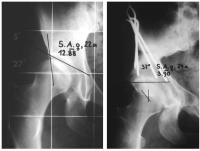

Abbildung 7: Frühstadium mit beginnendem Kondensationsstadium links. Sowohl auf der ap-, als auch auf der axialen Aufnahme ist die angedeutete Verminderung der Höhe der Kopfkalotte mit leichter Verdichtung der Strukturen erkennbar.